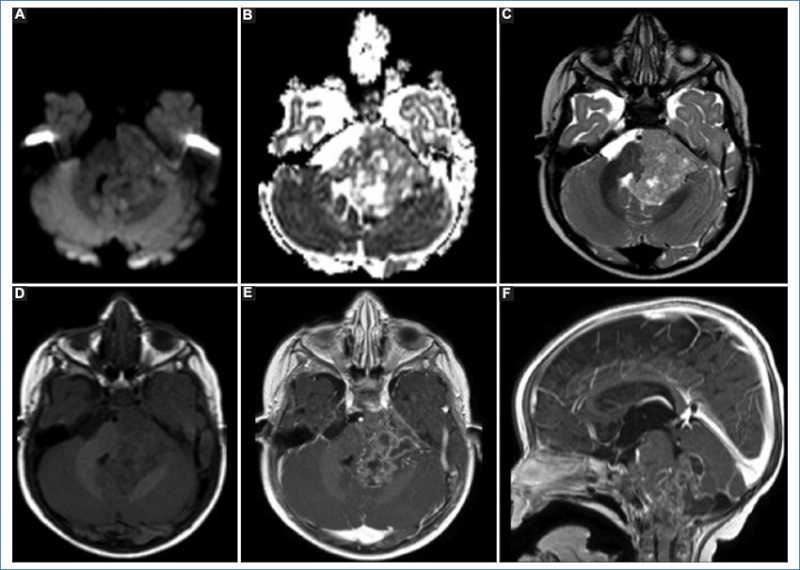

Los tumores de origen ependimario son el tercer tipo de tumor primario cerebral en pediatría, con un pico dentro de los primeros 4 años de vida y predominancia en el sexo masculino. Son más frecuentes en localización infratentorial, representando el 10-15% de los tumores de la fosa posterior7. Actualmente se clasifican, según su localización, en cinco grupos: ependimomas supratentoriales, ependimomas de fosa posterior grupos A y B, ependimomas medulares, ependimomas mixopapilares y subependimomas8. En nuestro estudio encontramos un solo caso de este tipo histológico, ubicado en la fosa posterior y con características propias de un tumor de grado 3. Se consideran de grado 3 aquellos con alta celularidad, atipia nuclear, hipercromatismo, marcada actividad mitótica y necrosis o proliferación vascular asociada. En los estudios por imágenes se encontrarán lesiones en la fosa posterior que nacen del piso del IV ventrículo, con extensión a los forámenes de Luschka y Magendie. Los ependimomas de fosa posterior del grupo A nacen principalmente del receso lateral del IV ventrículo, y tienen menores posibilidades de ser resecados que los del grupo B, que suelen nacer en la línea media. En la RM habitualmente presentan señal baja ponderada en T1 y heterogénea en T2, dado que en torno al 50% presentan calcificaciones y el 10% presentan hemorragia. En difusión muestran restricción intermedia, y el realce tras la administración de contraste intravenoso es variable en intensidad1. En nuestro paciente, el realce fue marcadamente heterogéneo debido a las múltiples áreas sólido-quísticas y focos de hemorragia (Fig. 2). Con independencia del grado de resecabilidad, en tumores considerados de grado 3 el tratamiento de elección es la radiación, viéndose mejores resultados cuando a esta le sigue la quimioterapia; en algunos pacientes se prefiere evitar la radiación y realizar solo quimioterapia debido a los efectos adversos en edades tempranas7. En nuestro paciente se decidió tratamiento únicamente con quimioterapia, sin evidencia de progresión de la enfermedad al día de hoy, pero con secuelas neurológicas como trastorno de la deglución y de la marcha.